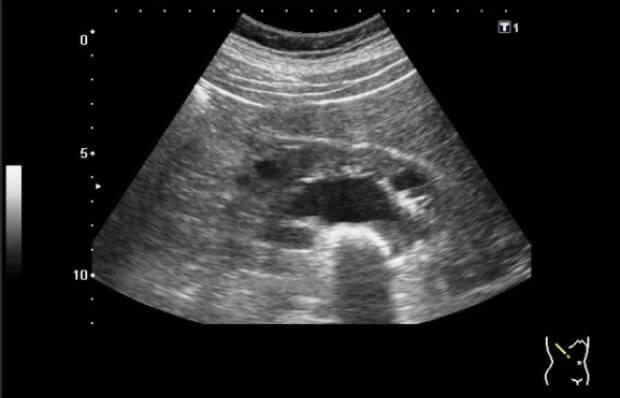

Egy hónap alatt az ultrahang kimutatta, hogy a ciszta kétszer zsugorodott - 20 mm-ről 10 mm-re! És a három kő közül kettő megolvadt és előkerült (Emlékszem, hogy ez előtt pár nappal fájt a vizelés). Aztán áttértem a normál adagra. Egy hónappal később az orvos megdöbbent, amikor ultrahangot végzett - a vesék tiszták voltak! emoji emoji emoji

before előtt

after után